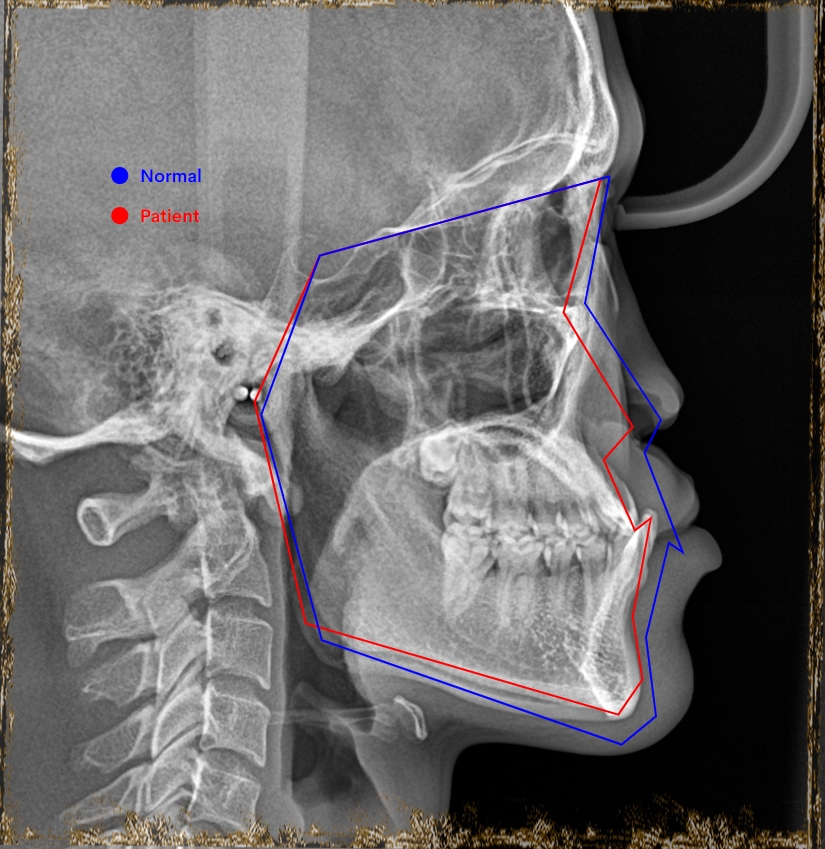

Đây là 1 case BN khe hở môi thiếu R11 bẩm sinh, trước điều trị là tình trạng hẹp hàm trên, cắn ngược hàm trên nghiêm trọng.